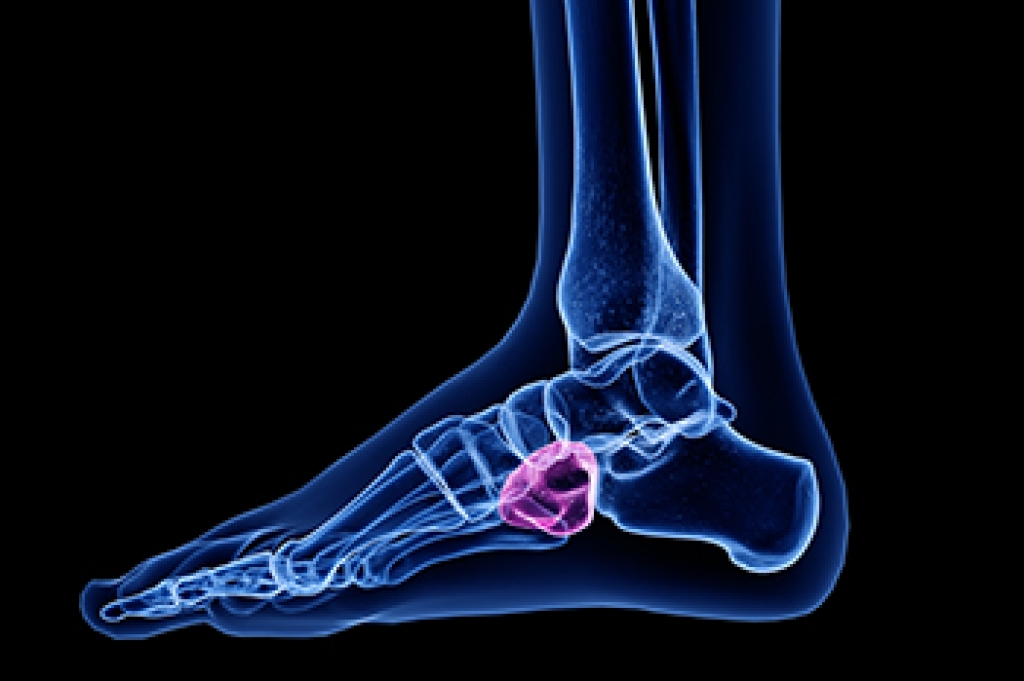

Cuboid syndrome is a common cause of lateral foot pain, which is pain on the outside of the foot. The condition may happen suddenly due to an ankle sprain, or it may develop slowly overtime from repetitive tension through the bone and surrounding structures.

Diagnosis of cuboid syndrome is often difficult, and it is often misdiagnosed. X-rays, MRIs and CT scans often fail to properly show the cuboid subluxation. Although there isn’t a specific test used to diagnose cuboid syndrome, your podiatrist will usually check if pain is felt while pressing firmly on the cuboid bone of your foot.